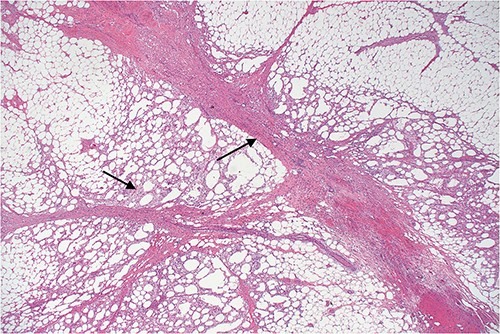

Histopathology revealed omental tissue measuring 170 × 135 × 52 mm with extensive fat necrosis and focal vascular thrombosis causing ischemic necrosis with congestion and some hemorrhage (Figs 8–10), in keeping with torsion and vascular obstruction. The inflammatory changes were not typical of mycobacterial infection and Ziehl–Neelsen staining for acid fast bacilli (mycobacteria) is negative. There was no dysplasia.

Lower power view of fatty tissue demonstrating a broad band of septal fibrosis, indicating a chronic inflammatory process. Adjacent fat is chronically inflamed and contains a dense infiltrate of foamy histiocytes and some lymphocytes, typical of fat necrosis.